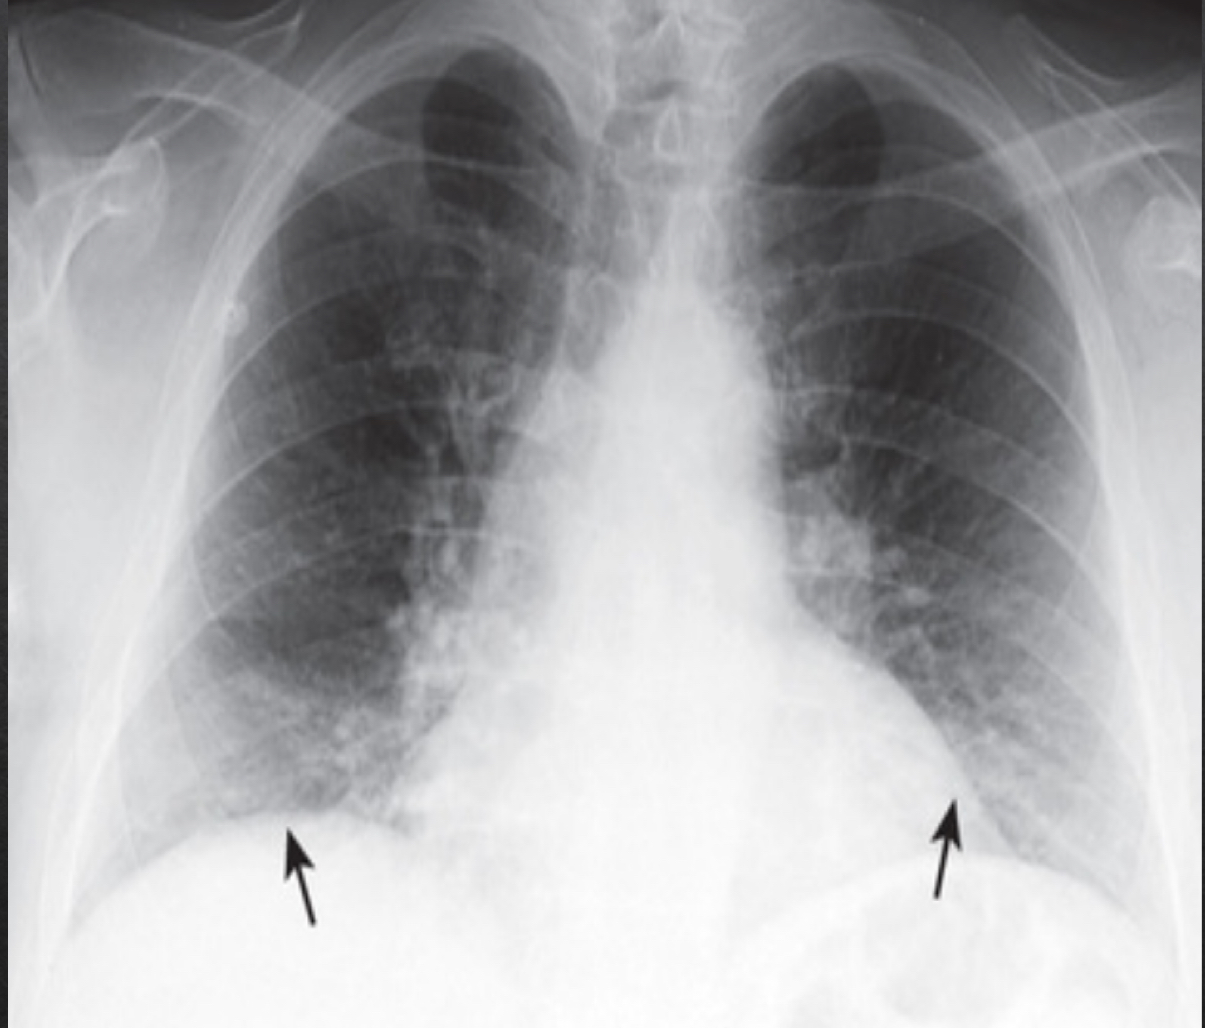

diaphragm: frontal view

right hemi

slightly more elevated

left hemi

no significant elevation

costophrenic angles

sharp